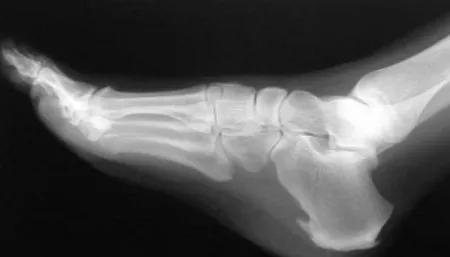

足底筋膜炎又称为“跖筋膜炎”,或俗称“跟痛症”,是指足跟和足底部分纤维组织出现的一种慢性无菌性炎症,是由足跟着地时反复高张力刺激足底筋膜的起点造成轻微的撕裂,引起囊腔状的退行性改变。

而骨刺就如下图中所示,则是这种慢性炎症反复刺激跟骨后产生的反应性增生,从一定程度上反而可以缓解疼痛。